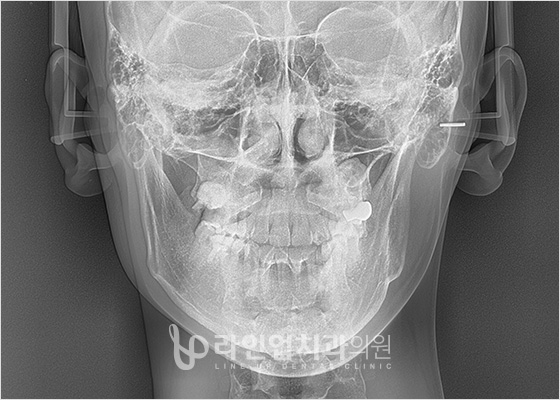

01 Компьютерная томография 3D

Система высокоточной трехмерной диагностики

позволяет в точности проанализировать не только лицевые кости, но и лицевые нервы, кровеносные сосуды и их расположение, а так же состояние мышц и жировой ткани, вплоть до строения и движения лицевых костей.

Изготовление точно подходящих костных имплантатов

идеально подходящий имплантат под форму кости пациента, в точности повторяющий поверхность кости